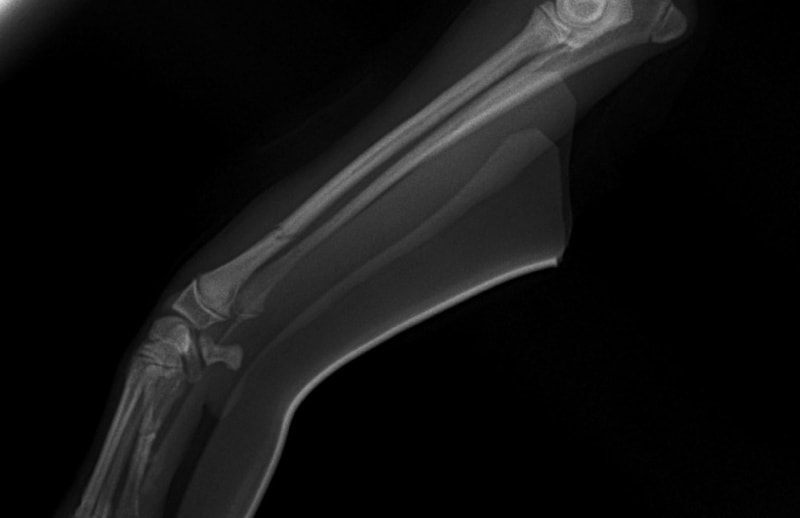

橈尺骨骨折 : 症例1 | 症例2 | 症例3 | 症例4 | 症例5 | 症例6 | 症例7

: 症例8 | 症例9 | 症例10 | 症例11 | 症例12 | 症例13 | 症例14

: 症例15 | 症例16 | 症例17 | 症例18 | 症例19 | 症例20 | 症例21

トイプードル 右遠位橈尺骨短斜骨折のALPSによる内固定